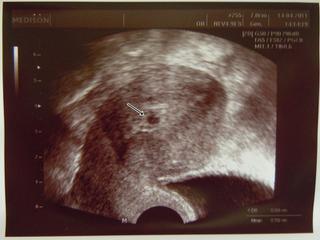

Holky, tak tady posílám fotečku ze včerejšího UTZ - 21.den po KET

@ronecek flek vidím, vidím tam i nějaké další, ale asi to bude to jedno, když to doktor říkal, on to umí poznat líp 🙂

@fiallinka Ahoj, no to já nevím. Na fotečce jde vidět jedno, ale doktor říkal, že zatím mi říct nemůže, kolik jich tam bude. Já myslím, že to zůstane u toho jednoho 🙂

@ronecek Krásná fotečka, fakt moc pěkná culíkatá holčička 🙂 a hlavně zdravá!!!